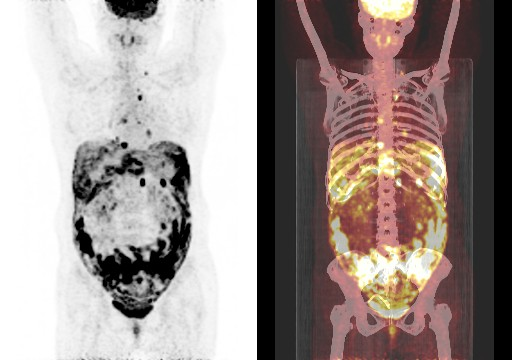

在全球,结直肠癌是发病率位居第三位、病死率位居第二位的肿瘤。肠镜筛查的普及以及手术方式的提升显著降低了结直肠癌的死亡率,但仍有一部分患者在初诊时已发展为晚期,失去手术根治的机会,且预后较差,5年生存率仅12%。许多转移性结直肠癌(mCRC)患者在经历一线治疗后,面临无药可用的困境。近年来,随着靶免联合治疗在系统治疗中逐渐前移,各种靶向治疗药物在mCRC的诊疗中也越发举足轻重。本文分享2例晚期结肠癌患者的诊疗经过,呈现瑞戈非尼在二线治疗为患者带来长生存的治疗价值及其良好的后线应用前景,以期为临床医生提供诊疗借鉴。 病例提供:海军军医大学附属长征医院 王湛 王湛 病例基本情况 一般信息:女 ,58岁。2020年10月,患者无明显诱因出现腹胀,无伴随症状,未予重视。后腹胀进行性加重,2020年11月中旬下腹部隐痛,与进食及体位变化无关,无肩背部放射痛。 辅助检查: 腹部超声:腹腔积液。 腹水脱落细胞病理:腺癌。 腹部增强CT:结肠肝曲癌;腹盆腔积液,腹盆腔腹膜多发转移。 结肠镜(2020-12-4):升结肠近肝曲见隆起型新生物,范围约4cm,新生物表面分叶状,质脆,触之易出血。肠腔狭窄,内镜尚可通过。 2020-12-8病理:横结肠,中分化腺癌,含部分粘液腺癌。 一线治疗2020-12-03至2021-02-24 CAPEOX+贝伐珠单抗 治疗4周期 病情进展,腹胀、腹痛加重,腹水增加。 2021-3-31 PET-CT:腹腔内及腹膜、脾脏、纵隔及右侧心膈角区、左侧锁骨区多发代谢增高灶,结合病史,考虑转移;双肺转移;腹腔及盆腔积液;结肠显示欠清,请结合肠镜检查;双侧胸腔少量积液,左肺下叶部分不张;双肺少许慢性炎症;右肝血管瘤;左肾结石。;子宫术后,痔疮可能;脊柱退变,腰3不稳,腰3/4、4/5、腰5/骶1椎间盘突出。 PFS:3个月 2021-4-6,完善基因检测(腹水标本):KRAS/APC/TERT/TP53/ target=_blank class=infotextkey>P53 突变,TMB 7.98/Mb,MSS 二线治疗,2021-04-02至2021-12 2021-3-31 2021-6-2 2021-8-6肠镜:结肠镜顺利插至回盲部,回盲瓣呈唇状。结直肠粘膜呈桔红色,光滑湿润,有光泽。血管纹理呈树枝状,清晰可见。 PFS:8月 三线治疗,2021-12-13至2022-01-23 三氧化二砷 2021-6-2 2021-11-22 2021-11-22 2022-2-8 PFS:2月 四线治疗,2022-02-10 化疗+免疫+瑞戈非尼+三氧化二砷 2022-2-10开始使用小剂量化疗(雷替曲塞+奥沙利铂+伊立替康)+免疫(信迪利单抗)+瑞戈非尼+三氧化二砷治疗。 疗效评估(2022-9-20):患者病情再次取得缓解。 2022-9-22至今采用维持治疗,降低治疗强度:雷替曲塞 +信迪利单抗+瑞戈非尼+三氧化二砷 2022-9-20 2023-2-8 PFS:13个月+ 该患者为中年女性,诊断为晚期多发转移性结肠癌,基因检测提示KRAS突变,BRAF、NRAS野生型,微卫星稳定,无法进行根治性切除。一线治疗加予CAPEOX联合贝伐珠单抗,治疗4周期后出现病情进展,腹胀、腹痛加重,腹腔积液增加,二线采用瑞戈非尼联合免疫和化疗,患者耐受良好,1周期后腹胀明显缓解,全身状态、PET-CT、肠镜结果较之前明显改善,继续原方案治疗,PFS长达8月。二线治疗进展后完善基因检测,发现TP53 突变,经与患者充分沟通,三线治疗采用三氧化二砷,疗效不佳。四线治疗在三氧化二砷基础上加用瑞戈非尼+免疫+化疗,患者病情再次取得缓解,PFS 超过13个月。近年来,随着精准医学及靶向、免疫治疗的发展,mCRC的管理与治疗策略的制定也变得复杂,合理选择治疗手段、优化全程管理至关重要。本例患者经历了一线化疗联合免疫治疗后疾病出现快速进展,我们个体化地在二线治疗中应用瑞戈非尼联合方案,患者疾病得到控制,PFS 8个月。在四线治疗方案中,再次挑战瑞戈非尼,依然获得较好的疾病控制效果,目前PFS已超过13个月。基于CORRECT和CONCUR研究,瑞戈非尼用于mCRC三线治疗已积累大量临床数据,目前已成为mCRC三线标准治疗方案。此外,REGONIVO、REGOTORI以及RIN方案证实了瑞戈非尼联合免疫治疗MSS型肠癌取得更长的总生存期。一线治疗后疾病进展,能否将瑞戈非尼使用前移,在二线治疗中加用以进一步延长患者生存,以及前线已经暴露过瑞戈非尼,后线再次使用瑞戈非尼是否可行,仍待在临床研究中进一步证实。 02 病例分享二 病例提供:海军军医大学第一附属医院 王薇 王薇 病例基本情况 一般信息:男性,41岁。2020年10月8日,无明显诱因下出现便血,为鲜红色,伴肛门坠胀不适,无排便习惯改变,无腹胀,无消瘦。1997年因“胃溃疡”行胃部幽门切除术;2019年行混合痔手术。 辅助检查: CEA 3.4ng/ml,CA199 3.52u/ml。 当地医院肠镜(2020-11-20):(距肛缘8-10cm)可见粘膜不规则隆起,表面溃烂,易出血。 肠镜活检病理:(直肠)中分化腺癌。 盆腔MRI增强(2020-11-26):直肠中段癌,考虑mrT3N1Mx,MRF-,EMVI-。 肝脏MRI增强(2020-11-27):未见明显异常。 治疗经过 首次手术治疗2020-12-09 腹腔镜辅助直肠癌拖出式适形切除术+末端回肠造口术 术中探查:直肠下段肿物,质硬,未浸润浆膜层,周围系膜未见肿大淋巴结。肿瘤大小约4*4*2cm,占肠腔1/2周,系膜完整。 术后病理: 直肠溃疡型肿瘤大小4.5x3.5x1.5cm;中至低分化腺癌,部分为粘膜腺癌;浸润至外膜层; 癌结节( 3枚+)、脉管癌栓(+)、神经侵犯(+)、肿瘤出芽(+,PDC1级);上下切缘(-)、环周切缘(-)、吻合圈(-);周围淋巴结(2/6),直肠外膜淋巴结(2/4),最高群淋巴结(0/4); 基因分型:KRAS Exon-2 G12D突变,NRAS、BRAF、PIK3野生型;免疫组化:MSH2(+),MSH6(+),MLH1 (+),PMS2(+),pMMR;Ki-67 80%。 术后分期:pT3N2aMx IIIB期 术后辅助治疗(XELOX方案) XELOX方案化疗3周期; 拟行盆腔放疗50gy/25次,2021-03-25起放疗6次 术后复查 肝脏MRI增强(2021-03-27):肝脏多发结节,较前为新发,考虑肝内多发转移瘤 一线治疗,2021-04-22至2021-06-24 mXELIRI+贝伐珠单抗 治疗4周期 患者治疗后出现恶心呕吐,胃纳明显减退,Ⅱ°粒细胞下降,腹泻,脱发,轻度手足皮肤反应,手足冰凉,心悸。患者无法耐受继续治疗 维持治疗,2021-7-15至2021-8-26,卡培他滨+贝伐珠单抗,共计治疗3周期 肝脏MRI增强(2021-5-31、2021-8-24):肝右后叶上段7mm小结节灶,转移不除外,腹膜后稍大淋巴结较前相仿,随访。 2021-3-27与2021-5-31的肝脏MRI增强对比图 2021-8-24 肝脏MRI增强 盆腔MRI增强(2021-8-25):术区及骶前软组织肿胀,左侧条索影,结合CT考虑术区置管术后改变,较2021-06-01片大致相仿。 疗效评估:PR 后患者诉心悸、乏力、胃纳不佳;血压正常;心肌酶正常;心脏彩超LVEF 64%;EKG: 窦性心率,T波低平;尿蛋白(-)。患者对化疗非常抗拒。 二线治疗,2021-09-17至2021-12-15 盆腔MRI增强(2022-9-13):术区及骶前软组织肿胀,左侧条索影,结合CT考虑术区置管术后改变,较前片大致相仿。 胸部CT(2022-9-13): 右肺下小结节,随访。 疗效评估:PR。 2022-12-20肝脏MRI增强:平扫+增强未见明显异常。 2022-12-21盆腔MRI增强:直肠癌术后,盆腔区未见明显复发及转移病灶。 病例总结 该患者为中年男性,诊断为局部晚期直肠癌,原发灶术后分期IIIB期,基因检测KRASExon-2G12D突变、微卫星稳定。术后仅3月余在XELOX方案辅助化疗、盆腔放疗期间出现多发肝转移,疾病进展转移灶不可切除,进而接受XELIRI方案联合贝伐珠单抗二线全身治疗。治疗后肝脏多发转移瘤退缩理想,病灶明显缩小减少。但患者治疗副反应不可耐受,改卡培他滨联合贝伐单抗治疗后持续有效,但仍无法耐受副反应。遂予以瑞戈非尼靶向治疗:120mg日剂量口服,服用三周停用一周至今。患者耐受良好,近期复查未发现明显复发转移病灶。目前二线PFS已达23个月,瑞戈非尼二线维持治疗DoR17个月。目前,二线治疗在不同患者亚群的优选方案仍存在争议。而整个系统治疗到了三线阶段,标准治疗主要价值是能够延长患者的疾病控制时间,缩瘤效果和客观缓解率均不理想,并没有满足目前的治疗需求。根据目前的药物机制和临床研究结果,考虑到患者的具体情况:涵盖治疗目标、体质状况、对预估的不良事件的耐受性及是否存在相关危险因素、既往治疗用药情况等方面,我们采用了个体化的瑞戈非尼二线维持治疗方案取得良好疗效,这种治疗策略希望能在规范临床研究中证实。病例分享一